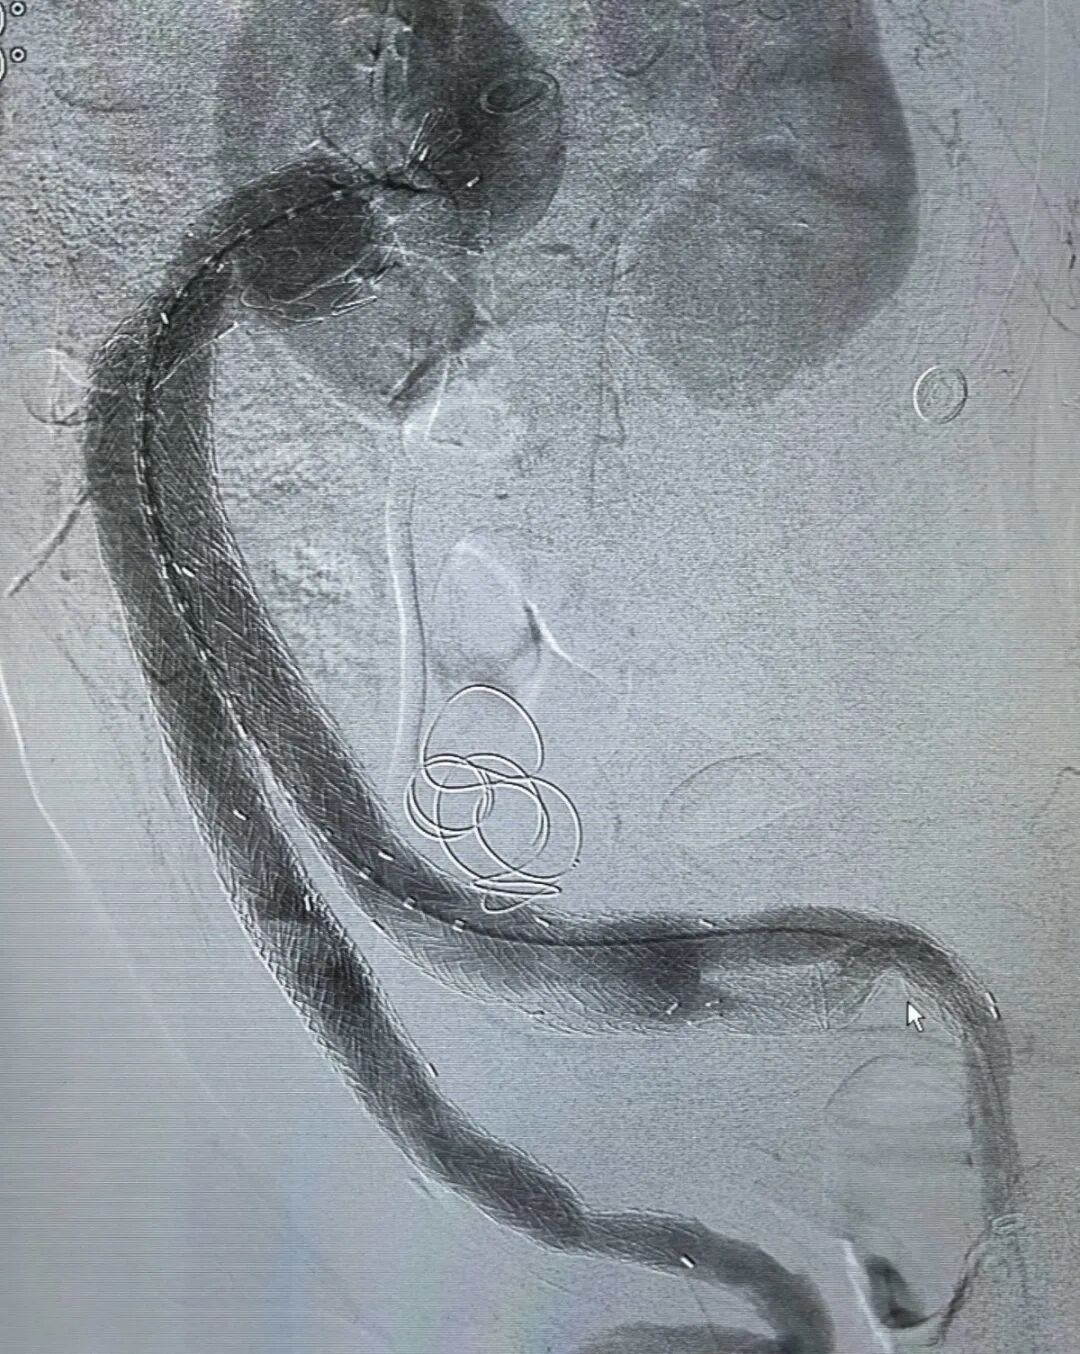

术前术后造影对比

手术过程中,在DSA影像设备的精准引导下,张永臻医师团队默契配合、操作娴熟,小心翼翼地操控导丝与支架,逐步穿越扭曲且严重钙化的血管段,最终成功将支架精准释放并固定于病灶部位。术后即时造影显示,支架位置理想,动脉瘤被完全隔绝,腹主动脉、双肾动脉及双髂内动脉血流通畅,无任何内漏情况,手术达到预期效果。